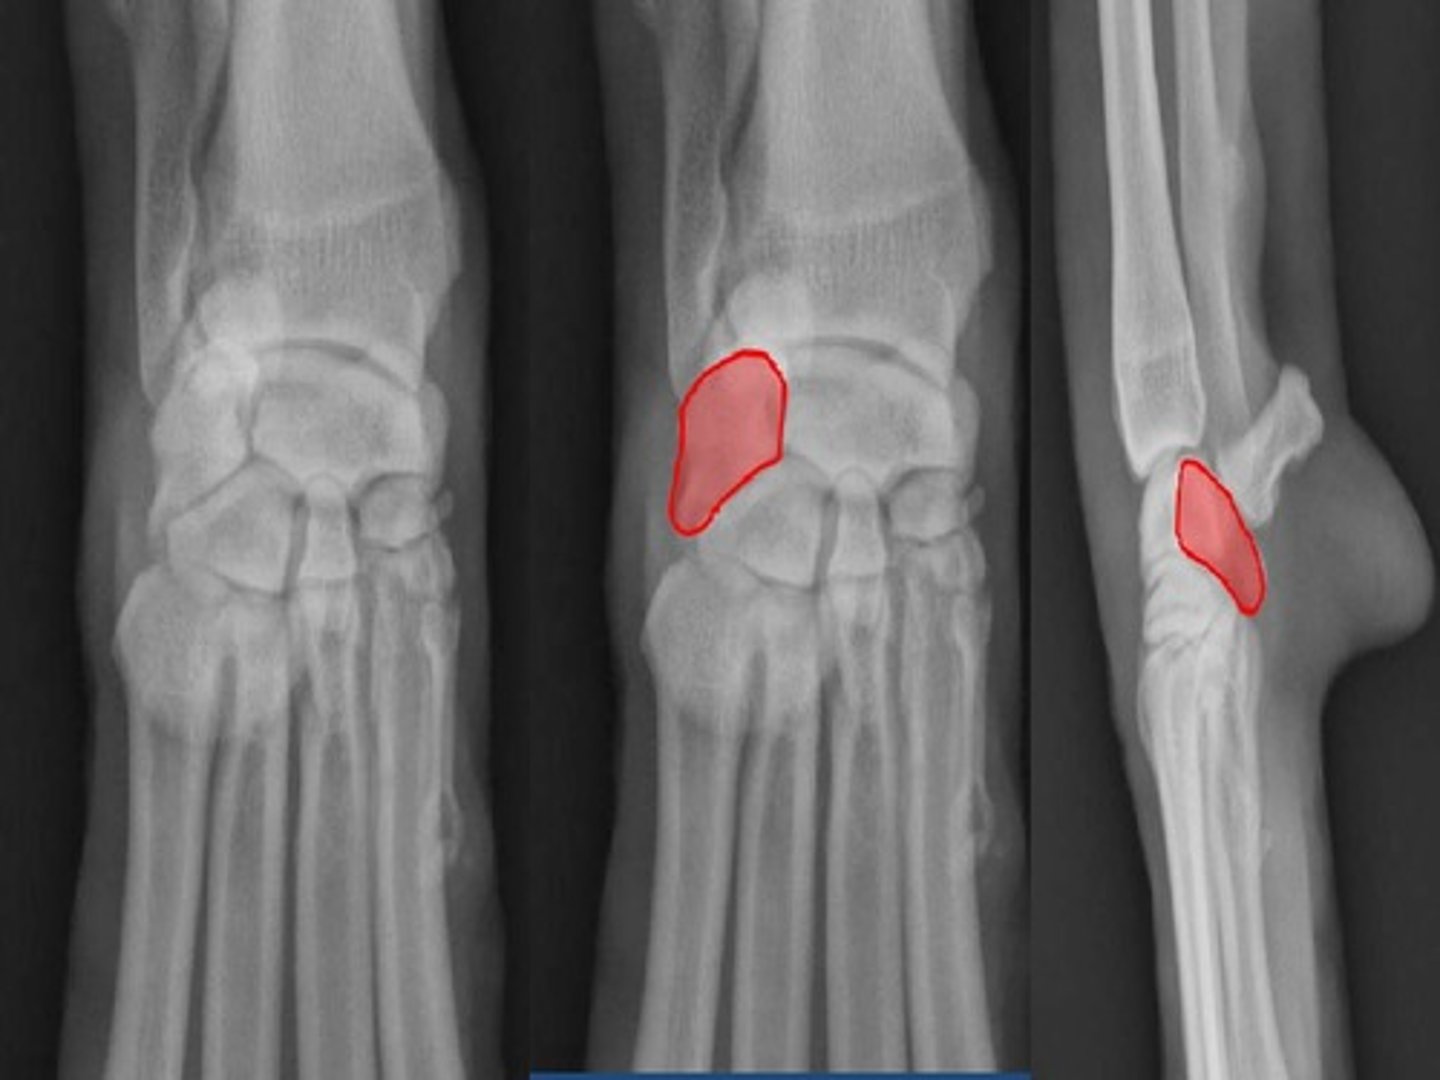

New cards

ulnar notch

the slightly concave area that articulates with the ulna. This sits on the lateral surface of the trochlea of the radius

<p>the slightly concave area that articulates with the ulna. This sits on the lateral surface of the trochlea of the radius</p>

44

styloid process of radius

the rounded projection on the medial surface of the trochlea of the radius

<p>the rounded projection on the medial surface of the trochlea of the radius</p>

45